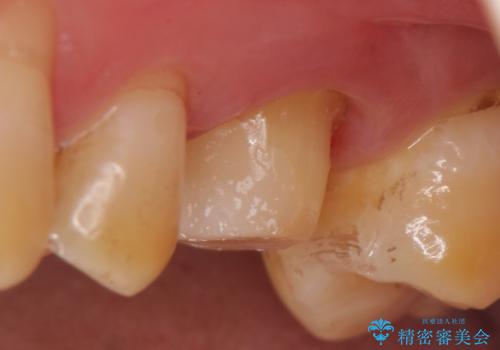

- 他院にて左上6番目の歯の神経が死んでいるといわれたので診て欲しいといらっしゃった方の症例です。

診査の結果左上6は失活していたため、根管治療を行った後にオールセラミッククラウンによる補綴を行いました。